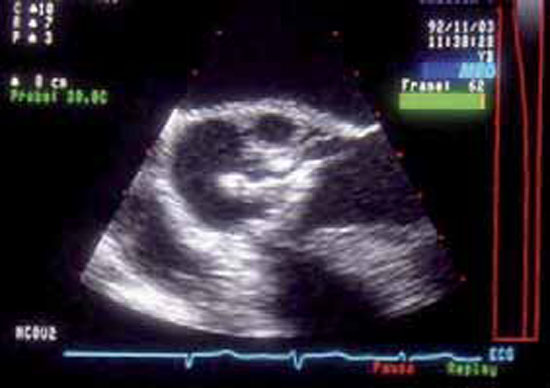

La végétation est une masse mobile, hyperéchogène, finement vibratile, attenante aux valves, et de taille variable. Elle est identifiée par l’échocardiographie transthoracique (ETT) ou l’échographie transoesophagienne (ETO) surtout en cas de prothèse valvulaire. Il faut savoir répéter l’ETO, la végétation pouvant apparaître secondairement après un premier examen normal (figures 1 et 2).

Figure 1 : Endocardite infectieuse (EI) aortique

Échographie transthoracique (ETT). Coupe grand axe parasternale gauche. Très longue végétation (2,3 cm de longueur), fine et mobile, attenante à la face ventriculaire de la valve aortique.